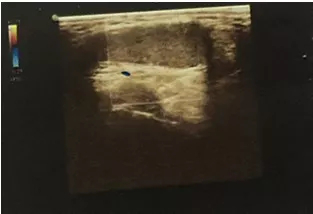

泌尿外科收治一名18歲男性青少年,反復(fù)右側(cè)睪丸疼痛2天,2天前出現(xiàn)右側(cè)睪丸疼痛稍腫脹,無其他不適,查陰囊彩超:右側(cè)睪丸、附睪較左側(cè)明顯增大,右側(cè)附睪頭實(shí)質(zhì)回聲增強(qiáng)不均,雙側(cè)睪丸、附睪血流信號(hào)未見明顯異常,當(dāng)時(shí)予對(duì)癥處理后疼痛好轉(zhuǎn)后回家。

近日,患者疼痛腫脹加重,再次至我院急診,行急診陰囊彩超:右側(cè)睪丸腫大回聲異常并其上方異常回聲區(qū),未見明顯血流信號(hào),未排睪丸扭曲可能,左側(cè)睪丸、附睪位置偏高,血流分布尚正常。